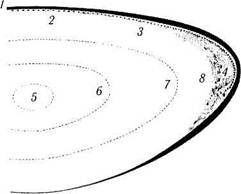

Рис. 3.4.13. Формирование швов в месте стыка волокон, происходящее в различные периоды жизни:

/ — Y-образный шов, формирующийся в эмбриональном периоде; 2 — более развитая система швов, возникающая в детском периоде; 3 — наиболее развитая система швов, обнаруживаемая у взрослых

Основное значение швов заключается в том, что благодаря такой сложной системе контакта между клетками сохраняется форма хрусталика практически на протяжении всей жизни.